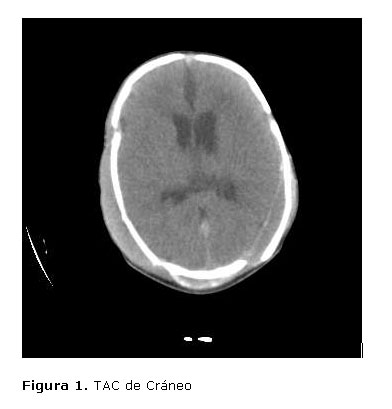

Su evolución posterior se caracterizó por un mejoramiento de su estado general, permitiendo comenzar la reducción de los parámetros ventilatorios y preparar las condiciones para el destete del mismo, lo cual se pudo realizar. Se le realizó TAC  de cráneo, donde se apreciaron signos de HSA a nivel de fosa posterior, con ligeros signos de hidrocefalia y sangre en el cuarto ventrículo,  hematoma subgaleal parietal bilateral, hematoma subdural izquierdo e  imagen hipodensa a nivel de la fosa posterior, con ligeros signos de edema periventricuar izquierdo pero sin efecto de masa( figura 1).

Fue interconsultado con el especialista en  Neurocirugía, el cual consideró que al no existir efecto de masa, ni signos de compresión de tallo cerebral, no  existía criterio de conducta quirúrgica.